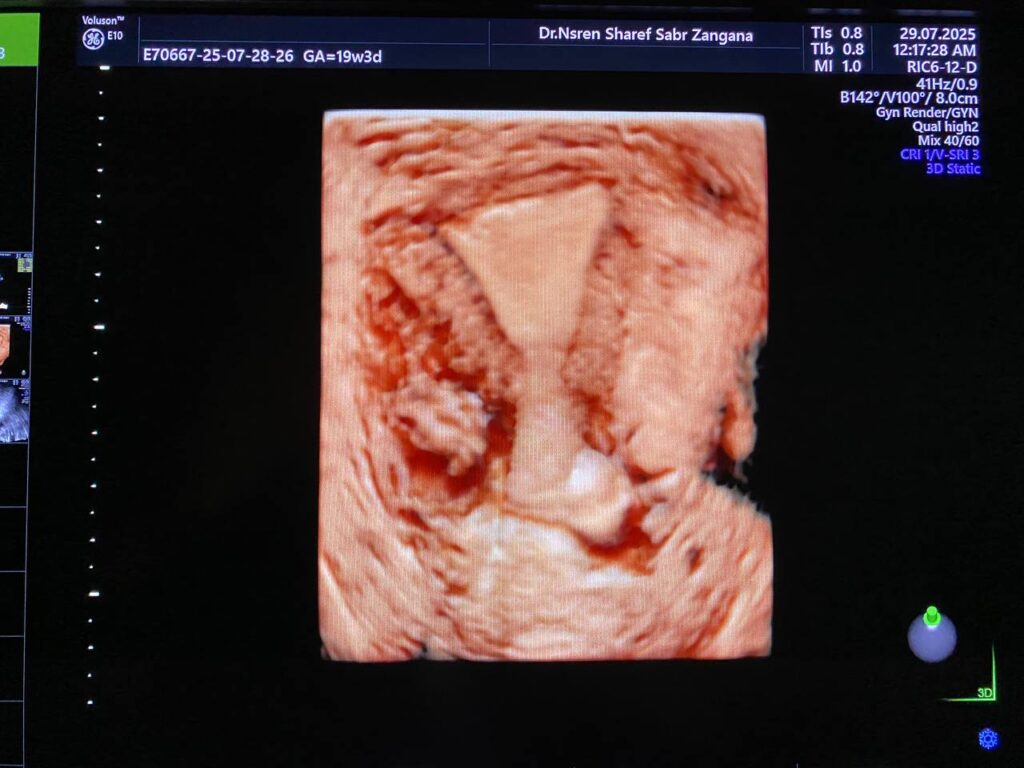

Bulky size A/V uterus, endometrial lining thickness 13mm, with presence of heterogenous cystic lesion in the right sided lower lateral body 22x2mm , mostly accessory cavity uterine malformation ACUM, no fibroid, single Nabothian cysts in the anterior lip of the cervix, its size11x8mm .